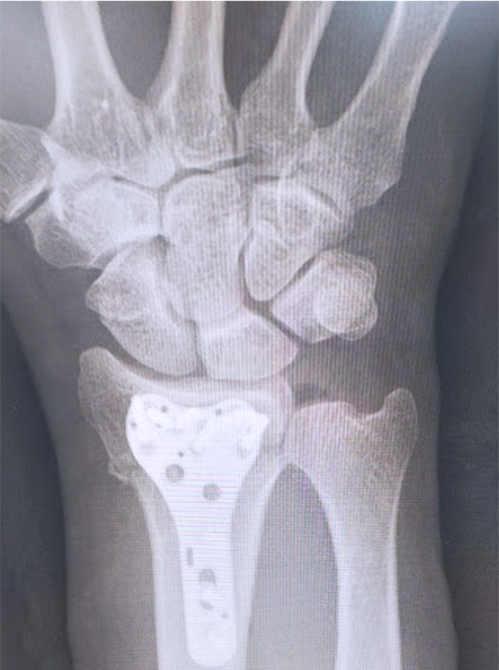

橈骨遠位端骨折に対する骨接合術